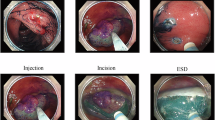

The dataset described in this paper comprises recordings of TEMS procedures performed on patients with early rectal cancer or large pre-cancerous polyps37. During the TEMS procedure, an operating scope is inserted trans-anally into the rectum. This is a stable and flexible platform that enables surgical access from the anorectal junction to the most cephalic aspect of the rectum. The top of the rectum is roughly 15cm from the anal verge (bottom of the anal canal). Most of the rectal lumen can be reached with this TEMS operating scope. The surgeon adjusts the scope to reach and remove the tumour, manoeuvring it as needed. The procedure begins with a setup phase, which includes preparing the scope, instruments, and the surgical site. The rectum is inflated with carbon dioxide to a preset pressure, and faecal debris and fluid are removed with a suction device to obtain clear views. The main phase involves dissecting the tumour, removing the specimen, and closing the rectal wall defect. Surgeons use a clockface analogy to navigate around the lesion site, facilitating precise removal. Dissection may be partial (mucosa and submucosa) or full thickness (deeper muscle tissues).

During dissection, multiple small events like surgical “smoke” fogging the lens, lens wash, tissue cauterisation, tissue retraction, fluid aspiration, and bleeding may occur. These are inter-related, for example tissue cauterisation results in surgical smoke that fogs up the operating scope and is normally managed by scope wash to clean the camera lens and aspiration of any fluid in the field of view. Bleeding is controlled with diathermy instruments and aspiration. Various instruments are used based on surgical needs. After dissection, the specimen is removed through the scope for histological analysis. In the closure phase, the surgeon uses a running suture to close the rectal wall defect. This involves handling the needle, driving it through the rectal wall, and pulling the suture to fully close the defect. Figure 1 illustrates the key steps of the surgical workflow for the entire TEMS procedure.

TEMS surgical workflow. A typical surgical flow from landmarking of the rectal polyp to dissection, lesion removal and closure of the rectal wall defect. The key milestones of a TEMS procedure are detailed in images a-j: [a] Baseline lesion in view after setup; [b] Application of landmark “dots” to outline the lesion; [c] Dissection of the wall through the mucosa and muscle; [d,e] Circumferential removal of the lesion; [f,g] Final removal and extraction of the specimen; [h,i] Closure of the rectal wall defect with a suture; and [j] Application of a metal clip to secure the suture and ensure complete closure.